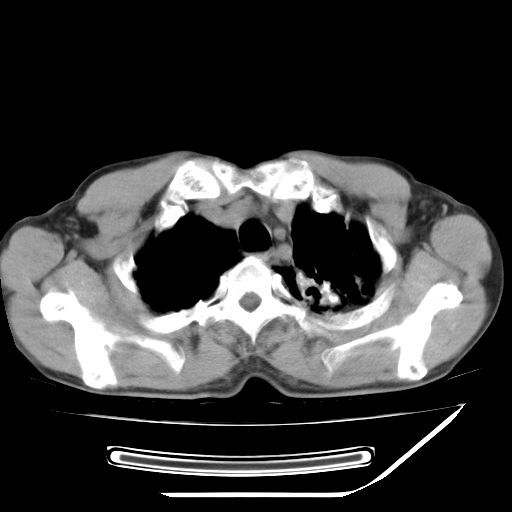

男,59岁,“结核性胸膜炎”30余年,胸部经常疼痛,多次x检查提示“肺部”炎症。腹部疼痛5日,b超提示:“肝内短管结石,余显示不清,建议进一步检查。”

两肺结核并右侧胸腔积液;脾脏、腹腔及腹膜后淋巴结结核[陈旧性];肝内胆管结石

胸部腹部都是结核(双肺。纵隔淋巴结,肝脏,脾脏,肠系膜)